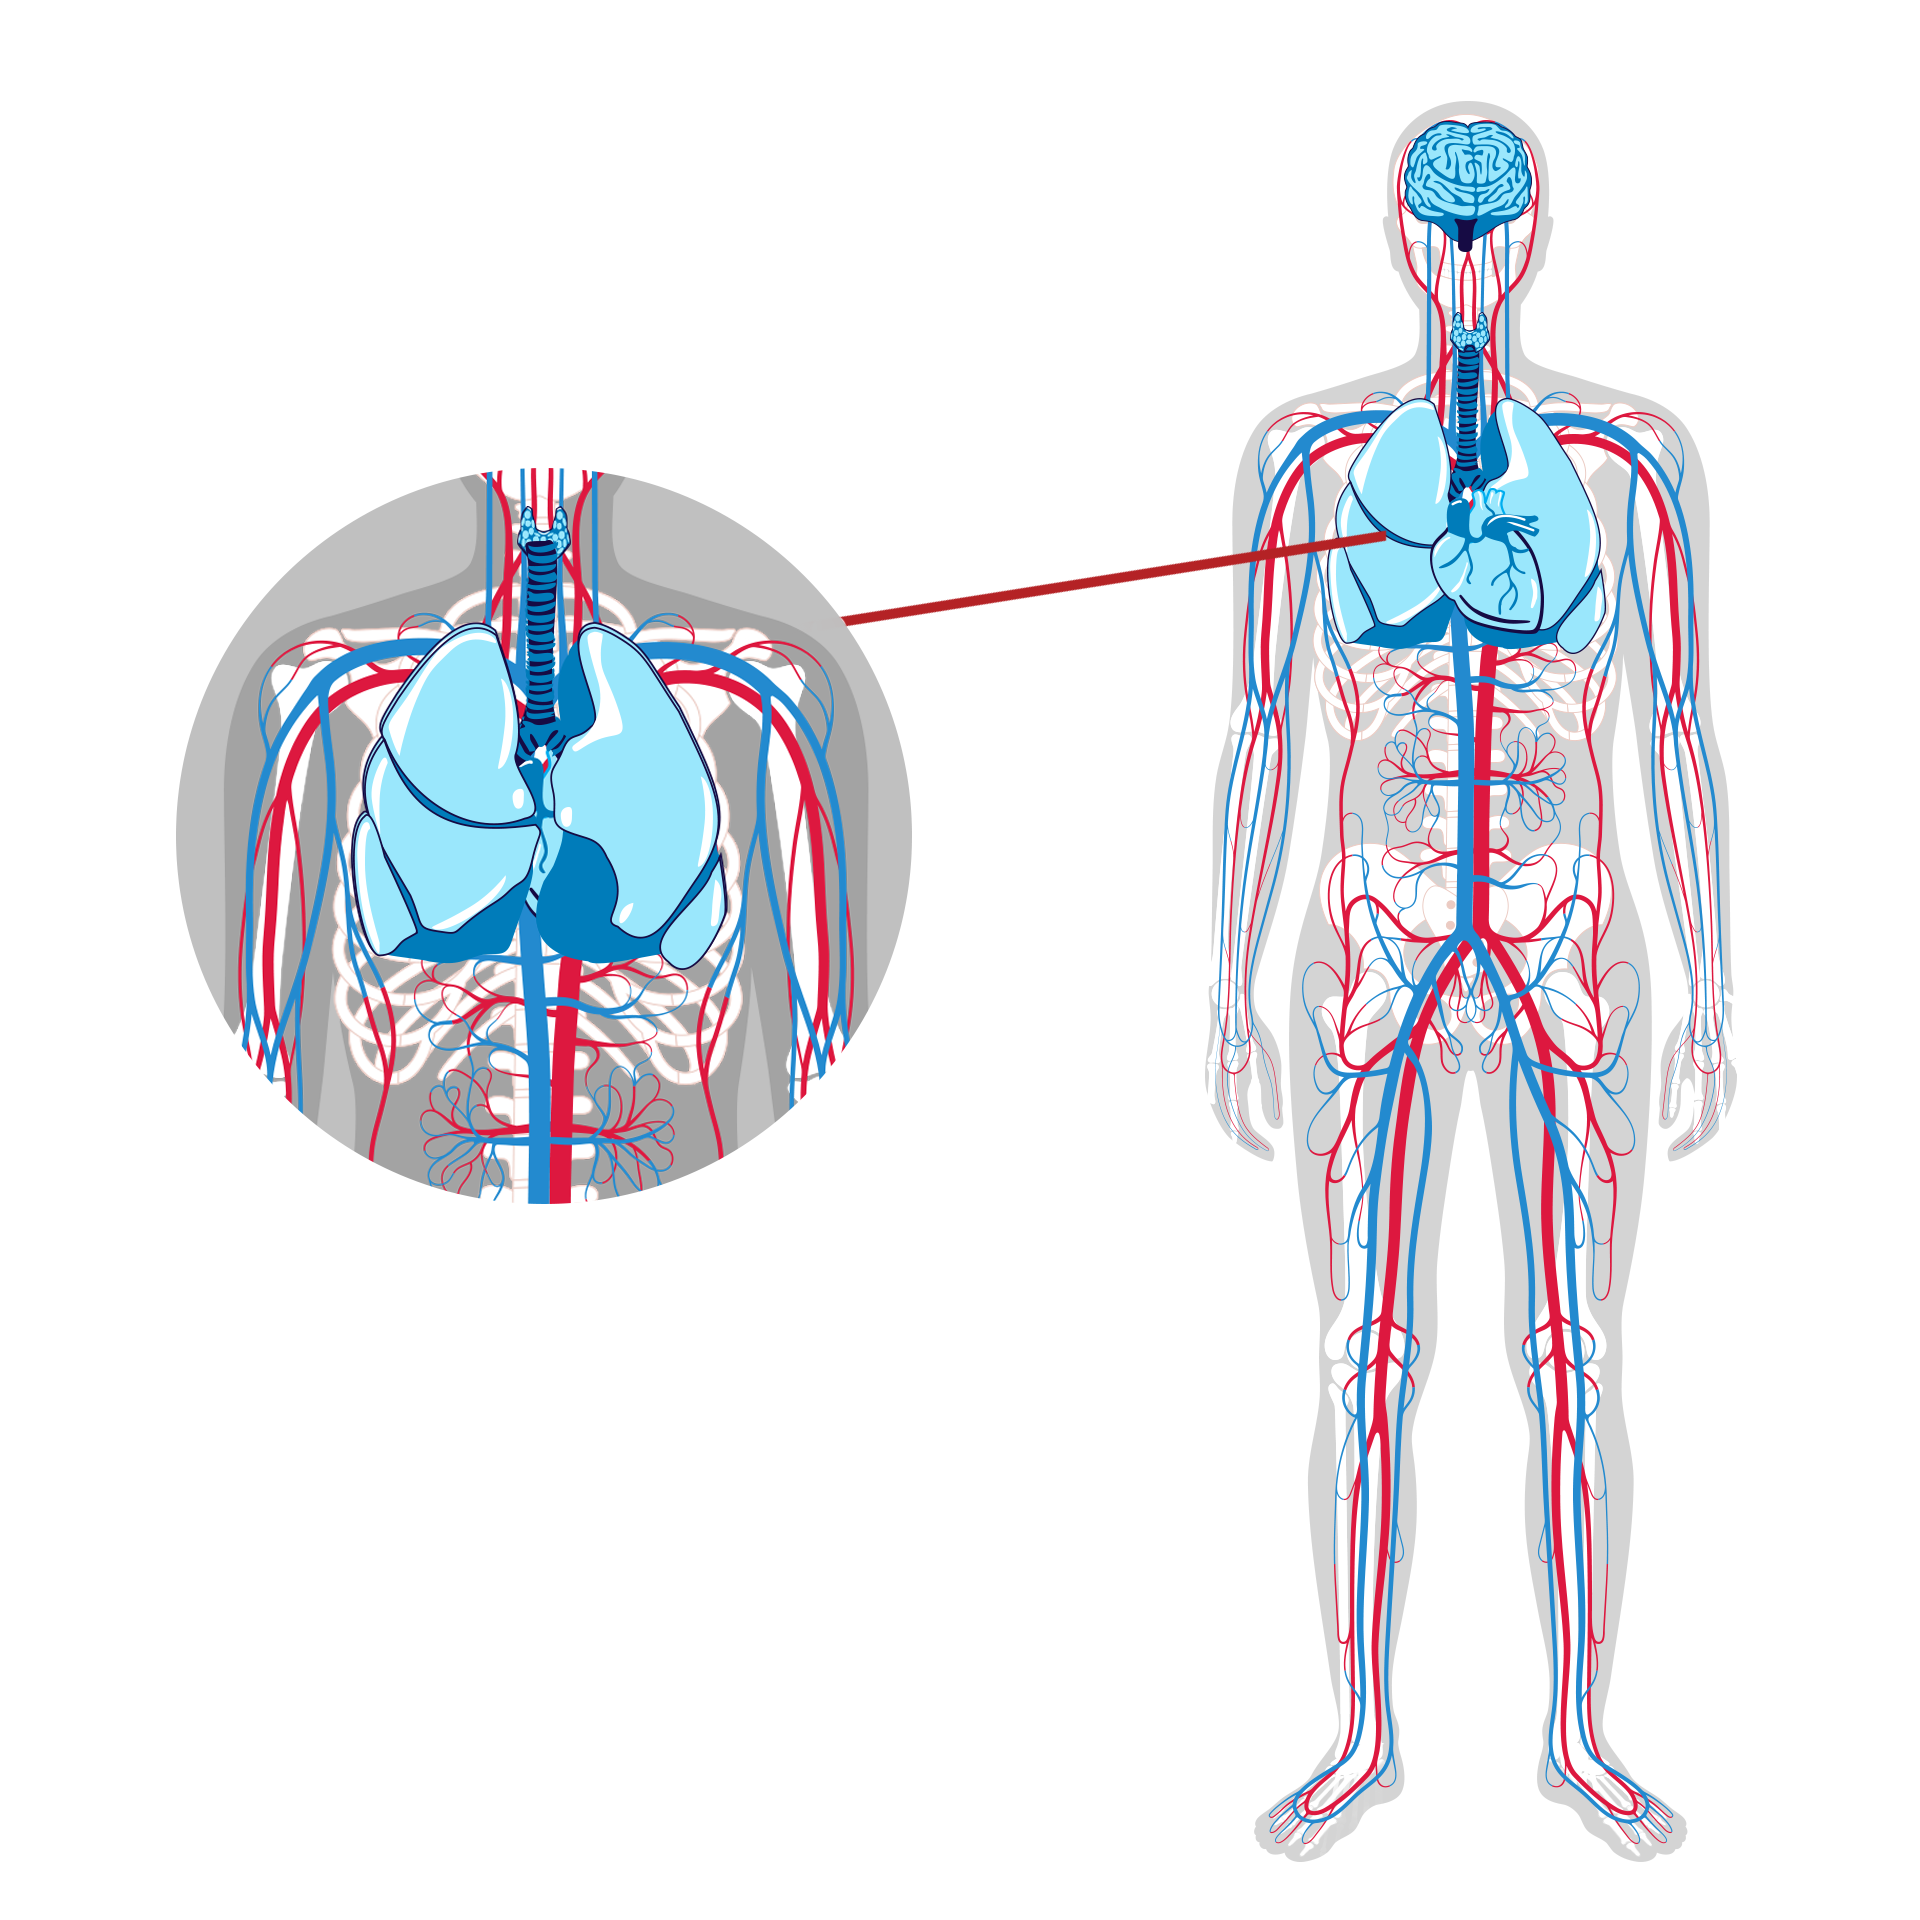

AREAS OF STUDY

TGB actively broadens our pre-clinical testing initiatives to assess the therapeutic potential of our products across a diverse spectrum of conditions, with primary focus on the brain, lungs and central nervous/inflammatory system(s). Our unwavering commitment to rigorous research positions us at the forefront of innovative therapies in this theater of study.